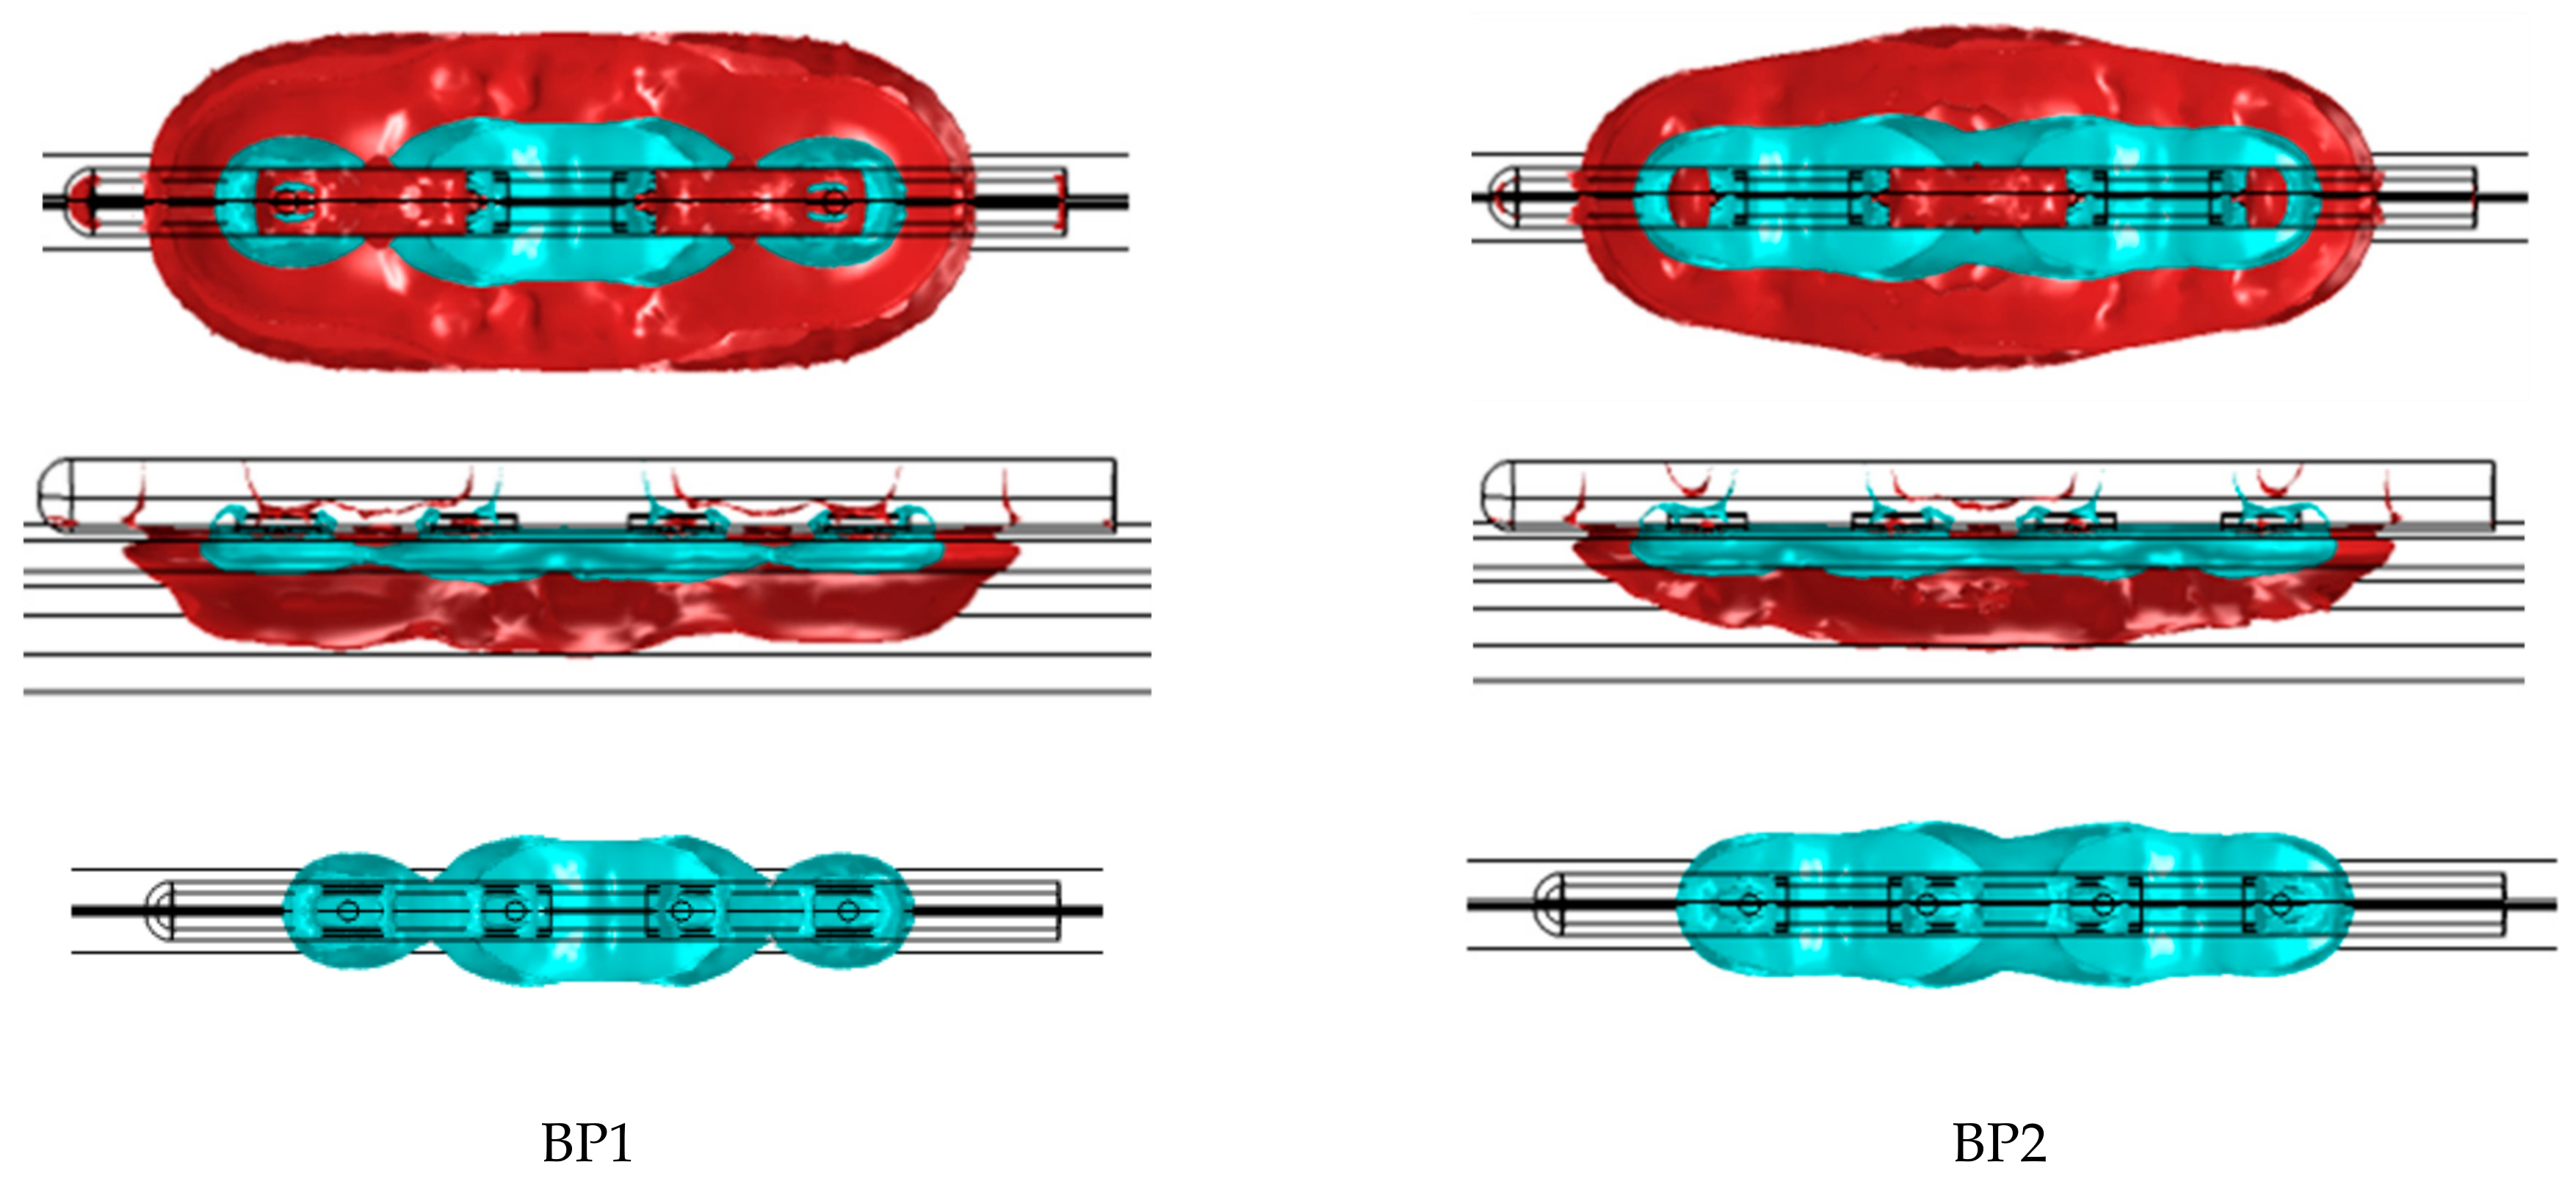

2.1. Ablation System Designs

2.2. Electric Field Modeling

3.1. Electric Field Models